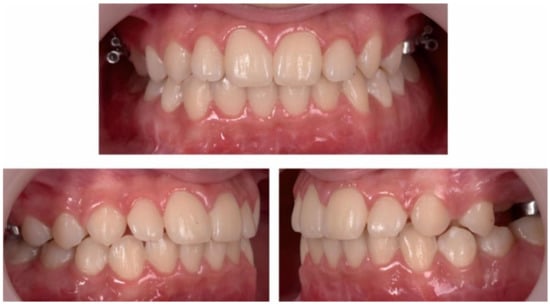

3. Results